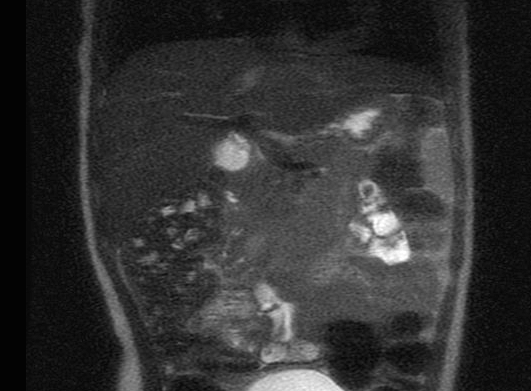

Since the care was established has been challengeable to control intensity and severity of seizures. There is a list of medications that was tried and failed as known as VPA, Topiramate, Zonegran, Felbamate, ACTH, Vigabatrin, Ketogenic diet and VNS(do not work in high parameters, currently on minimal parameters). In a first approach we add lamictal in a progressive way, stood with clobazam, rufinamide and we consider to enroll her in everolimus trial. After nephrologist, cardiologist and ophthalmologist evaluation we started work up preparation for everolimus use. Was ordered lung function test, BUN, creatinine, ALT,AST, CBC, Lipid profile, glucose level, HbA1,CMP, UA, urine culture, chest X-ray, brain MRI, Neuropsychological testing and Everolimus level in 2 weeks from start. Except for Brain MRI that showed 2 small SEGAs over the foramen of Monro; no other alterations was found and the drug was initiated at the dose of 3mg.

MRI demonstrate numerous subcortical hamartomas

MRI demonstrate subependymal nodules near the foramina of Monroe bilaterally

After 4 weeks of use she had an improvement on the facial angiofibromas, she became more social and had less spasticity over the upper and lower extremities, but her alkaline phosphatase went up 20 times and we had to stop it. At the second attempt of everolimus, her scalp skin was pilling off and on the third attempt she had bumps on her scalp that was showed by pathology be due to Staphylococcus. Therefor, the drug was stopped again and cephalexin was started and continued after the patient was cleared in a prophylaxis base to re-start everolimus. Once more we re-started the drug and for this time on the patient is having a good response with the medication without any major concerns We had a follow up brain MRI that showed multiple subependymal nodules with no change in size and number, and also a abdominal MRI which showed more than 100 angiomyolipomas(biggest around 1,2x1.4cm) . The patient is a close follow up with her nephrologist. During this time she still had refractory seizures with periods of worsening symptoms, but seemed to be in a better control (seizures every other day) with maximized dose of lamictal, Onfi and Banzel.

MRI demonstrate bilateral angiomyolipomas in the kidneys.